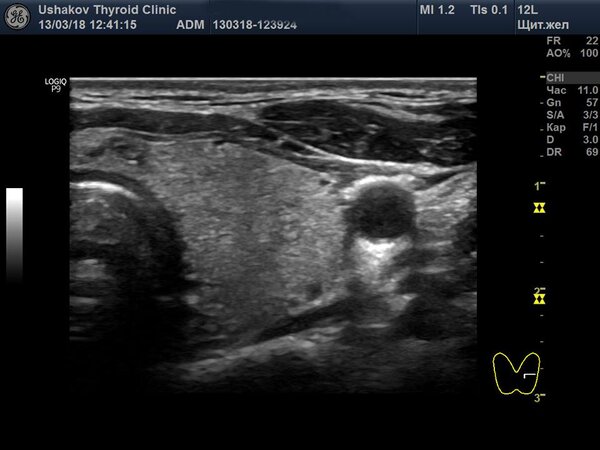

На этой неделе в нашей клинике был проведен осмотр пациентки, которая в 2001 году, в возрасте 13 лет, перенесла обширную операцию на щитовидной железе — так называемую 90% субтотальную субфасциальную резекцию. Это означает, что хирурги удалили почти всю ткань органа. Спустя 17 лет, во время ультразвукового исследования, мы с удивлением обнаружили, что все анатомические части щитовидной железы полностью восстановились, и визуальных признаков проведенной операции практически не осталось. Единственным напоминанием о хирургическом вмешательстве был тонкий, едва заметный рубец на коже.

Как же стало возможным такое полное восстановление? Во время операции хирург оставил примерно 10% ткани железы, преимущественно в тех областях, где проходят важные кровеносные сосуды и нервы. Пациентка в послеоперационный период не принимала заместительную гормональную терапию. Оставшаяся ткань, благодаря активной стимуляции со стороны нервной системы, запустила мощные процессы регенерации. В результате щитовидная железа не только восстановила свой первоначальный объем, но и полностью вернула свою анатомическую форму.